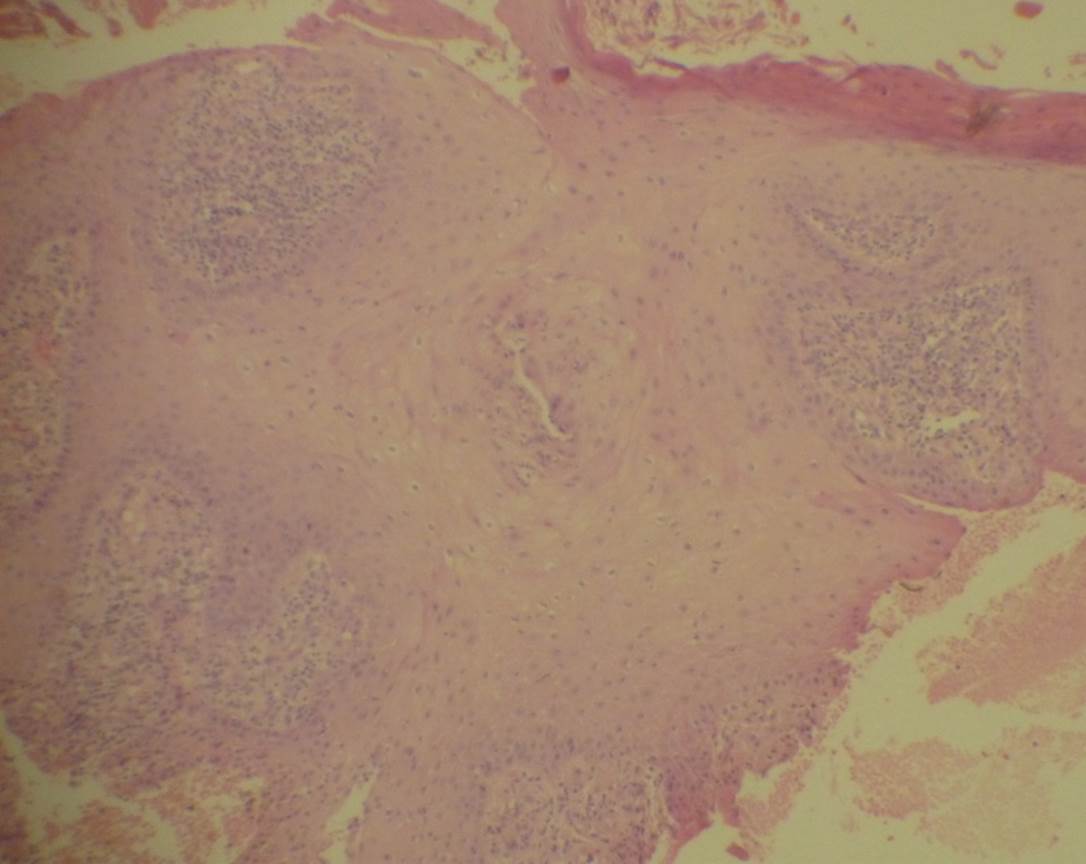

un caso de tuberculosis cutánea en rodilla izquierda en un adolescente

masculino de 15 años, cuyo diagnóstico se realizó a través

de un hallazgo histopatológico en la biopsia incisional de granuloma

por agente vivo y prueba terapéutica.

multidrug-resistant pathogens. The authors describe a case of cutaneous

tuberculosis on left knee in a 15 year old male, whose diagnosis

was made by the histopathological finding in the incisional

biopsy of a live agent granuloma and a therapeutic trial.